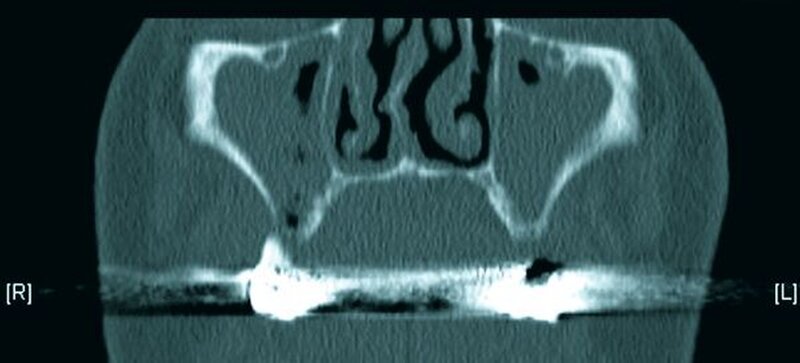

Die Computertomografie der Nasennebenhöhlen (NNH-CT) (nativ) zeigte dann das Ausmaß der knöchernen Destruktion. Neben der ausgedehnten generalisierten Nekrose des Oberkiefers konnte nebenbefundlich eine zystische Läsion im Bereich des Unterkiefers Regio 41 bis 45 diagnostiziert werden. Voraussichtlich ging diese vom Wurzelrest des Zahnes 41 aus. Weiterhin bestand eine totale Verschattung beider Sinus maxillaris und eine akzentuierte Lymphadenopathie in allen abgebildeten Leveln.